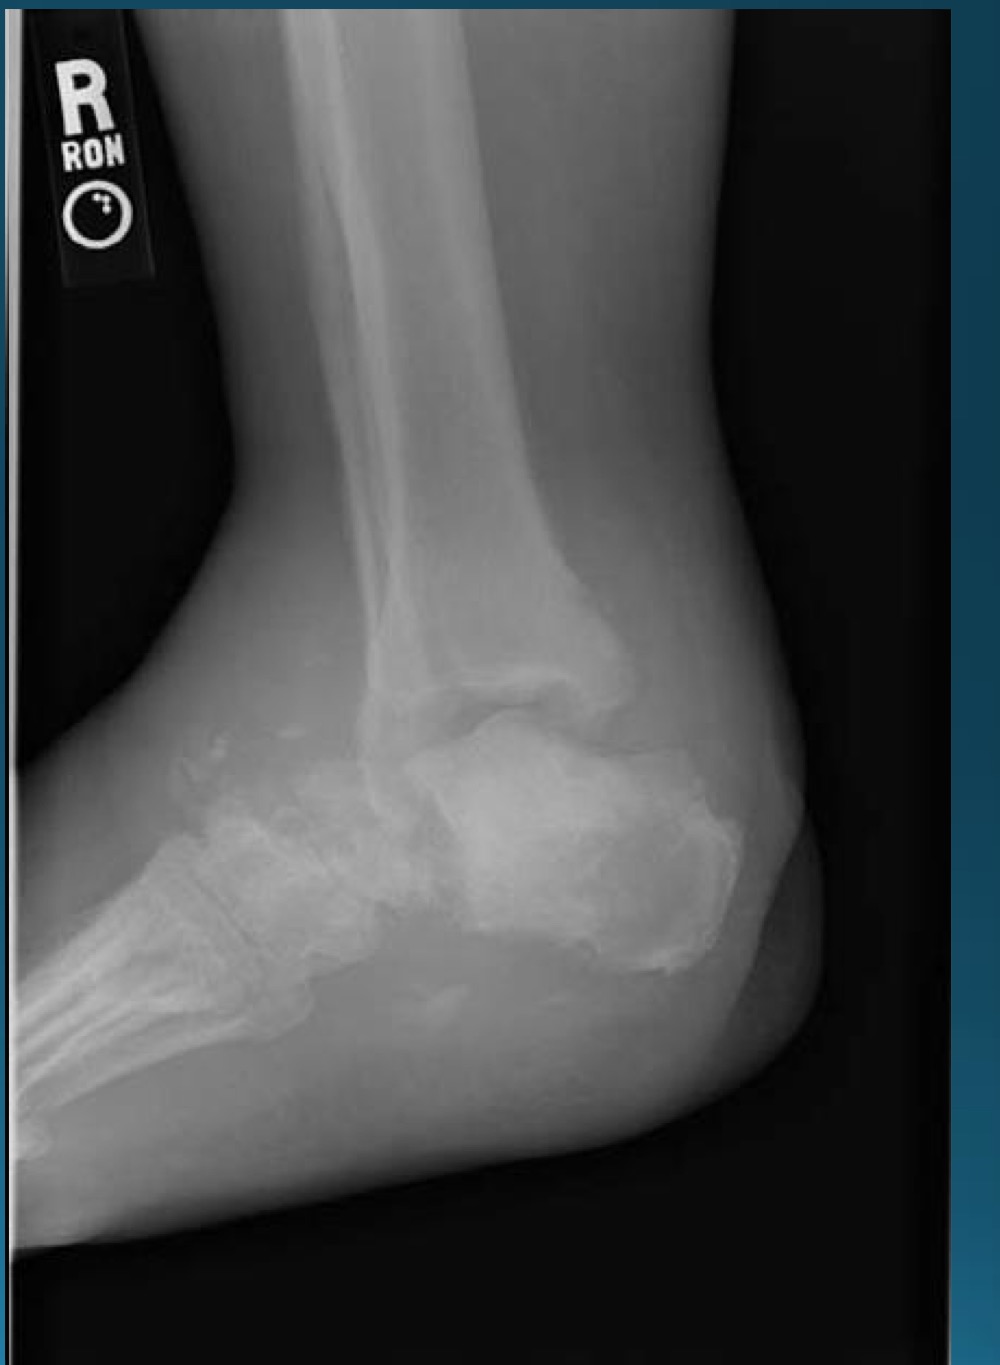

what is the finding in this radiograph? AKA?

what finding is in this image

hypertrophic neuropathic arthropathy

what is the finding in this image? AKA

neuropathic arthropathy AKA charcot’s joint

atrophic neuropathic arthropathy

what would this charcot joint be caused by

syphilis

syringomyelia

diabetes